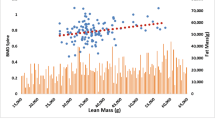

ROC curve analysis was performed to estimate the optimal cutoff value of FFM, FM, FM ratio, and BMR for predicting osteoporosis. As shown in Table 3 and Fig. 2, FFM showed an optimal sensitivity (0.588) and specificity (0.73) at the cutoff value of 37.9 kg (AUC = 0.700, 95%CI 0.646–0.753). FM revealed an optimal sensitivity (0.73) and specificity (0.47) at the cutoff value of 18.6 kg (AUC = 0.602, 95%CI 0.542–0.661). BMR presented an optimal sensitivity (0.59) and specificity (0.73) at the cutoff value of 1187.5 kcal (AUC = 0.701, 95%CI 0.647–0.754) while FM ratio did not statistically predict osteoporosis.

Previous studies reported that FM is related to the BMD of the lumbar spine and proximal femur [20, 21]. Besides, other studies showed that BMR is more closely related to BMD than FFM, FM, and BMI [18, 22, 23]. Our results were echoed to these studies and revealed that BMR could be effective to predict osteoporosis (BMD T-score < −2.5) with the optimal cutoff value of 1187.5 kcal (Table 3 and Fig. 2) in women over 50 years old. If their BMR was lower than the cutoff values 1187.5 kcal, they might have a high risk of osteoporosis.

BMR, the amount of energy expended, is predicted with regard to resting energy expenditure. In multivariate analysis, BMR was low correlated with FM (correlation coefficient 0.281) (Table 2), suggesting that BMR and FM might be independent predictors of osteoporosis. However, BMR is more closely associated with BMD in elderly persons than BMI, FM, and FFM [18, 22, 23]. BMR is positively associated with muscle strength [30] while muscle strength and BMD also are correlated [31, 32]. Our results also showed that the AUC of BMR is higher than FFM and FM, suggesting that BMR might be a good predictor for osteoporosis. According to our results, we proposed that if the postmenopausal woman’s BMR is lower than the cutoff value,1187.5 kcal, the subject might have a higher osteoporosis risk than others with over 1187.5 kcal. Although hip and spine fractures are a portion of osteoporotic fractures, these fractures have a huge impact on the patient’s daily activity and medical burden [33, 34]. Low BMD is associated with an increased risk of fracture and hence provided a measurable method in osteoporotic fracture preventions. However, the disadvantages are radiation exposure and limited accessibility. Since BMR could well predict BMD in the present study, it seemed a good method in screening osteoporosis. Besides, the American College of Sports Medicine (ACSM) proposes that increasing physical exercise can maintain and improve bone quality in response to bone health problems [35]. Here, we provided the cutoff value of 1187.5 kcal of BMR. It could serve as a target value for exercise intervention to enhance BMR in postmenopausal women to maintain and improve their BMD.